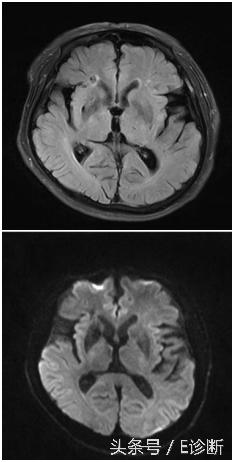

左侧基底节区亚急性期脑梗死,发病7天,T1WI为稍低信号,T2WI及flair像为高信号,DWI为高信号,ADC图为等信号,MRA示左侧大脑中动脉闭塞。